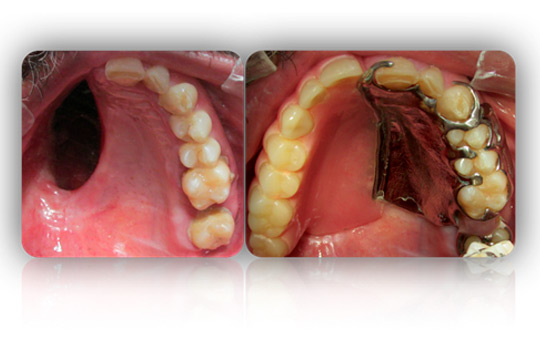

Rehabilitación integral en pacientes oncológicos con secuelas a causa de quimioterapia y/o radioterapia. Muchos tratamientos contra el cáncer tienen efectos secundarios que afectan la boca, los dientes y las glándulas salivales de un paciente. Estos efectos secundarios pueden hacer que sea difícil comer, hablar, masticar o tragar. Afortunadamente, con una buena atención y con nuestros tratamientos, es posible reducir el riesgo de estos efectos secundarios y manejarlos si se producen.